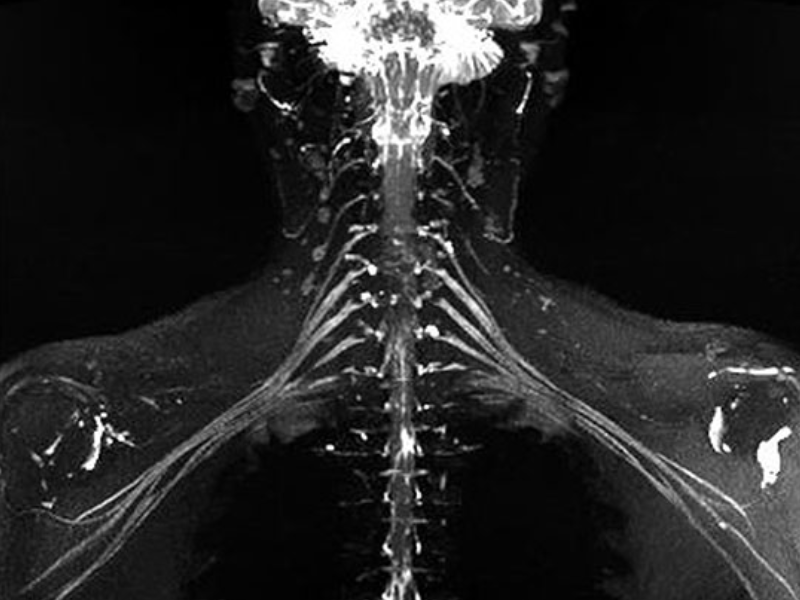

Prostate- DWI with post QUICK 3D